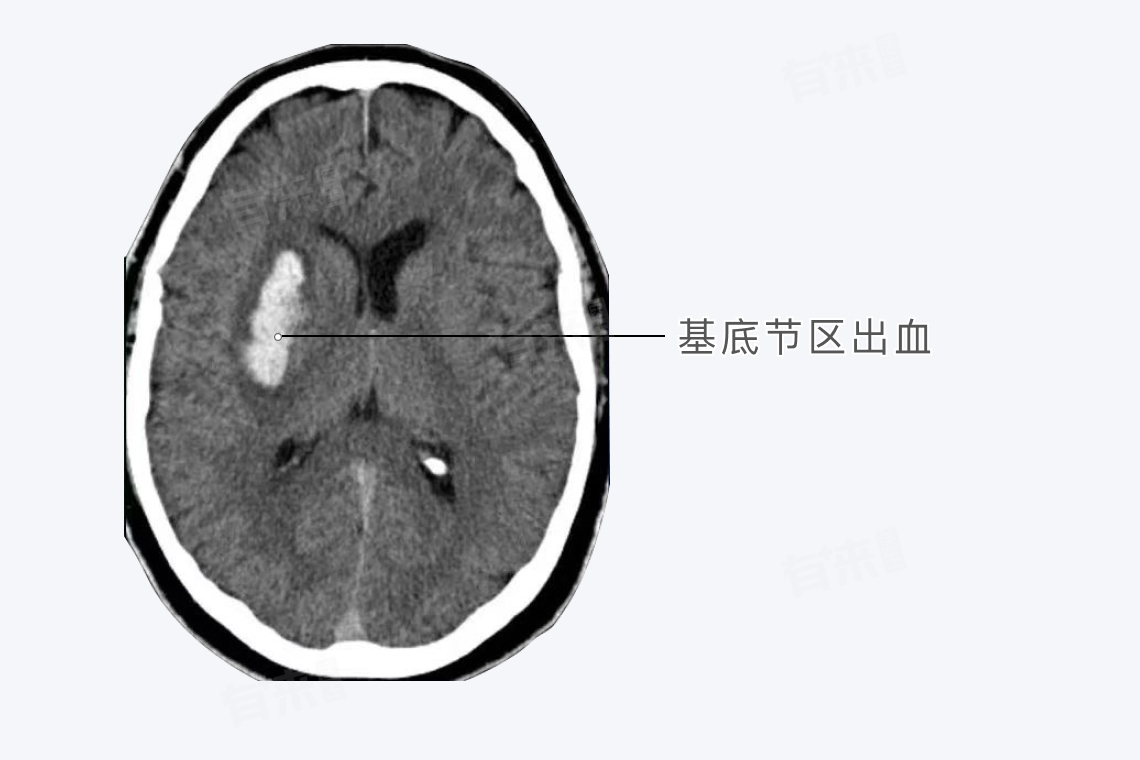

高血压脑出血最常见的出血部位是基底节区,这是由于血管结构特点和血管病变基础决定的,可导致偏瘫、偏身感觉障碍、同向性偏盲等症状。

基底节区的血液供应主要来自豆纹动脉,其从大脑中动脉垂直发出的细小分支,这些小动脉直接从较大的动脉主干发出,而且分支角度接近直角,这种特殊的血管结构使得豆纹动脉承受的血流压力较大,在高血压状态下,血管内压力持续升高。

长期高血压会导致脑内小动脉硬化,高血压使血管内皮细胞受损,血液中的脂质等成分容易沉积在内皮下,引起血管壁的玻璃样变和纤维素样坏死,这些病变使血管壁的弹性降低、脆性增加,在血压突然升高或波动时,容易发生破裂出血。